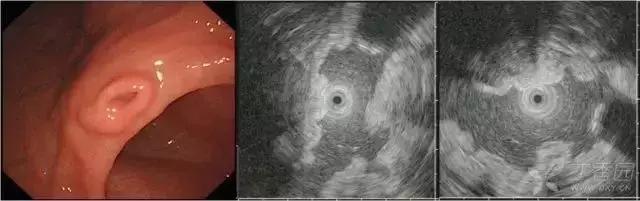

图 2胃神经内分泌瘤。白光下胃体下前壁可见扁平黏膜下隆起,表面可见血管显露,EUS 下黏膜深层-黏膜下层可见低回声病变